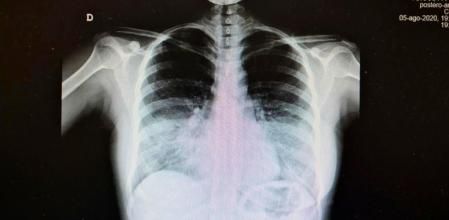

A ellos se ha querido dirigir Pascual Piñera, jefe del Servicio de Urgencias en el Hospital General Universitario Reina Sofía de Murcia, lanzando un aviso serio acompañado de un ejemplo más que gráfico tomado esta misma semana: la imagen de un paciente muy afectado por una neumonía bilateral producida por el coronavirus. Los pulmones son radiotransparentes y deberían verse negros enteros en una radiografía. En la base de ambos pulmones se ve opaco, lo que indica que hay afectación pulmonar por la COVID-19.

La imagen, que se ha vuelto viral, es bastante explicativa por sí misma: si no llevamos mascarilla y guardamos la distancia de seguridad requerida, esa radiografia podría ser de cualquiera de nosotros. Opiniones acerca de la imagen ha habido para todos los gustos. Sin embargo, sorprende cómo algunos usuarios insisten en que “tenemos que aprender a convivir con el virus” porque “no va a desaparecer” como respuesta a lo que están viendo; o criticar la labor del Gobierno, en lugar de aceptar que todos hemos de ser responsables y cambiar de hábitos una temporada.